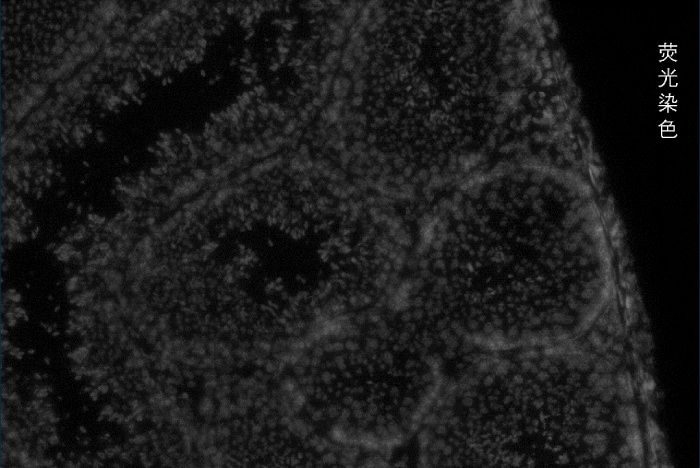

百創(chuàng )智造基于S系列空間芯片的底層設計,可以得到完全沒(méi)有錯誤的原片熒光圖像以及H&E圖像且與芯片完全對齊?;跓晒膺M(jìn)行細胞核的定位刻畫(huà)細胞核的邊界;基于HE的校準輔助刻畫(huà)細胞的邊界,通過(guò)邊界信息映射到芯片上,提取相應位置的測序數據,實(shí)現精準的單細胞分割。

2.原片熒光染色+原片H&E染色+原片空間測序相結合技術(shù):既可以進(jìn)行表達芯片H&E染色,又同時(shí)可以再表達芯片上進(jìn)行熒光染色,保證細胞分割更準確。